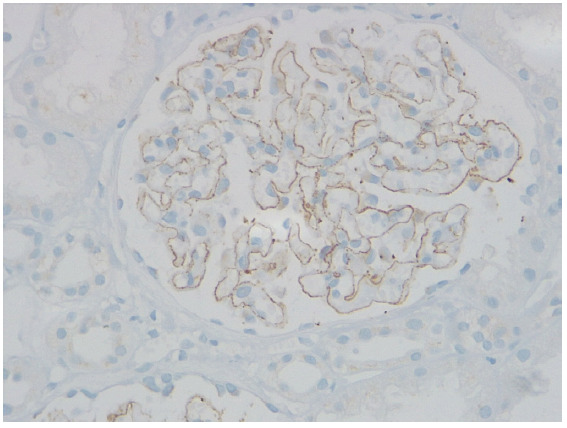

Membranous nephropathy (MN) is a rare autoimmune disease, in which the circulating autoantibodies against antigens attack podocytes. Neural Epidermal Growth Factor like 1 (NELL1) 1-associated MN is the second most common antigen, following phospholipase A2 receptor. Complementary and alternative medicine and malignancies play a pivotal role in the development of NELL1-MN. This retrospective study describes the clinical characteristics, therapeutic strategies, and longitudinal outcomes in patients with NELL1-MN at our center.

Abstract Image